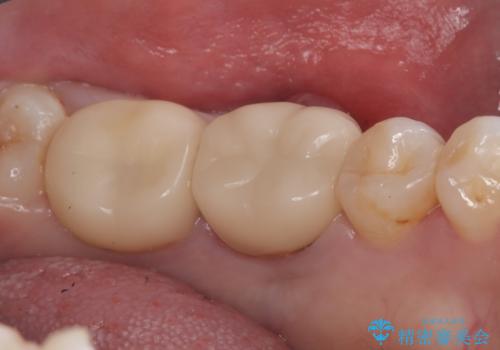

保存が難しい左下6番目の歯を抜歯し、左下8番目の歯(親知らず)を抜歯窩に移植しました。歯牙移植後の動揺防止のため暫間固定を行っています。

骨との定着を確認し、今後矯正治療を行う予定のためレジン冠をセットしています。